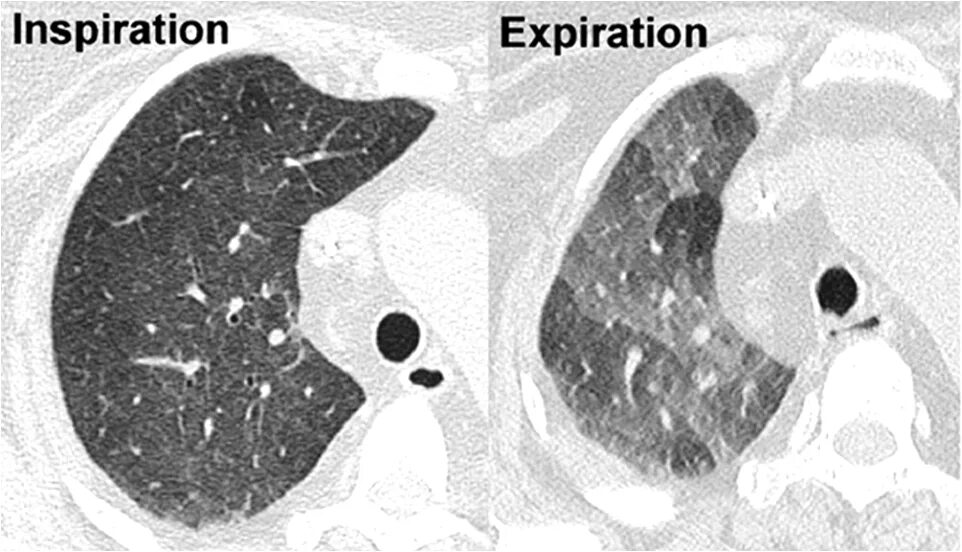

Мозаичная перфузия